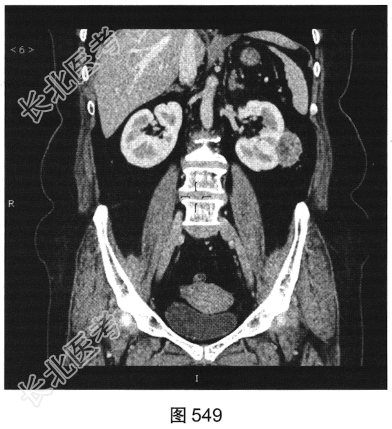

- 多项选择题3.[提示]CT平扫+增强(图545~图549):左肾下极背外侧软组织密度灶, 部分突出于肾实质外,其内可见低密度坏死灶, 增强扫描强化不均匀,平扫、皮质、实质、排泌CT值36HU、92HU、73HU、53HU。可考虑的鉴别诊断为( )

A、肾嗜酸性粒细胞腺瘤

B、出血性囊肿

C、肾血管平滑肌脂肪瘤

D、肾细胞癌

E、肾转移瘤

F、淋巴瘤